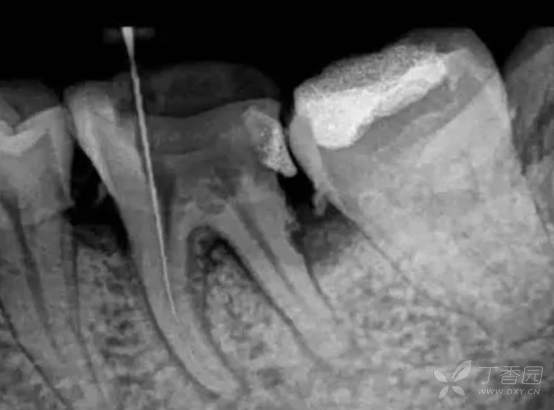

台阶多是由于在根管内使用刚性或直径较大的器械,并向根尖方向过度加力,器械不能顺应根管弯曲方向走行而嵌入根管侧壁,在局部反复切割导致根管侧壁形成类似“平台”样结构。根管内台阶形成的因素有许多,如牙齿解剖因素、操作者因素、再治疗因素等均会影响台阶的形成,临床医生应充分了解台阶形成的原因才能在临床操作中最大限度减少台阶的产生。

将10号手用锉锉尖1.5~3mm的部分预弯(根据实际情况,8号也可以),手术显微镜下观察根管的走向,预弯的根管锉滑入根管,然后根管冲洗,小幅度来回捻动根管锉,当根管锉越过台阶进入原有根管之后,先采用小幅度的连续上下提拉的手法,扩大和疏通台阶根方的根管,然后逐步扩大上下提拉的幅度,待器械松动并达到工作长度之后,将锉尖穿出根尖孔1mm左右,这样根尖孔的大小等于0.12mm,以便为15号手用锉的使用提供根管通路,与处理堵塞的根管不同的是,在疏通根管台阶的操作中,每当小号手用锉退出根管时,都用顺时针转动手用锉,因为这一动作使手用锉的锉尖1/3拉直,而台阶多位于根管外侧弯曲部,锉尖拉直的力量正好作用于台阶侧的根管壁,有助于去除或者减小台阶,若手用锉阻挡了操作者在显微镜下的视线,可换用专用显微锉并将锉尖预弯。